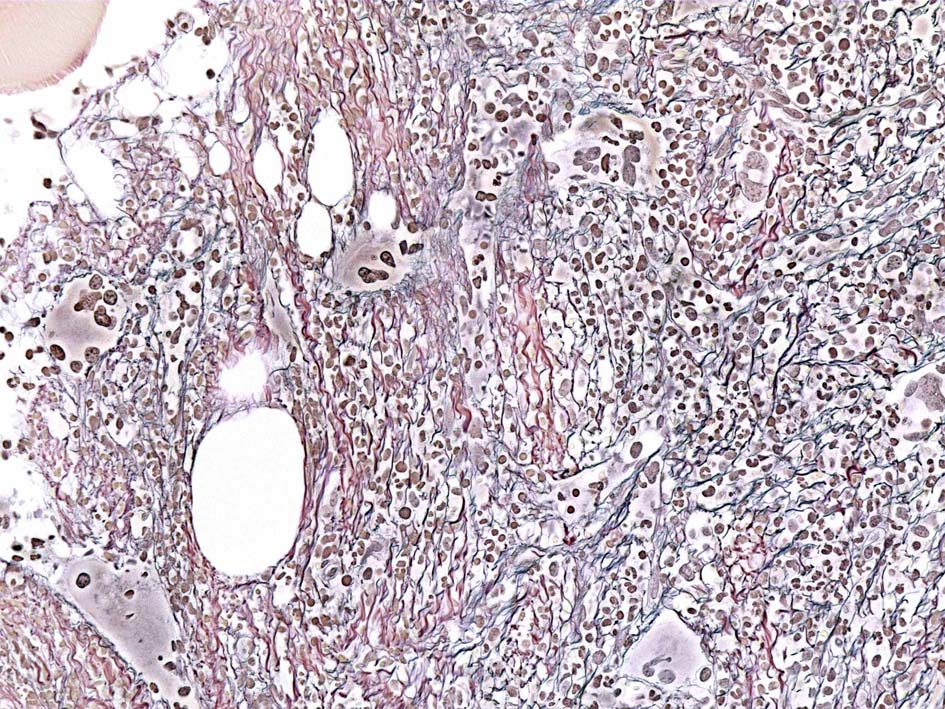

黒染する弾性線維の増生のほか, 赤く染まる膠原線維の増生が確認される. MF-2 fibrosis. 鍍銀染色の核染色をすると膠原線維の赤染がわからなくなるので行わない.